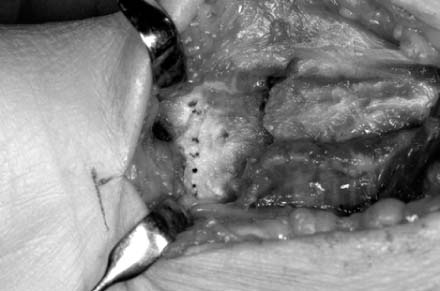

Fig. 10

A dotted line indicates transverse ridge, and the fracture site is exposed after elevation of pronator quadratus.

Fig. 10 A dotted line indicates transverse ridge, and the fracture site is exposed after elevation of pronator quadratus.